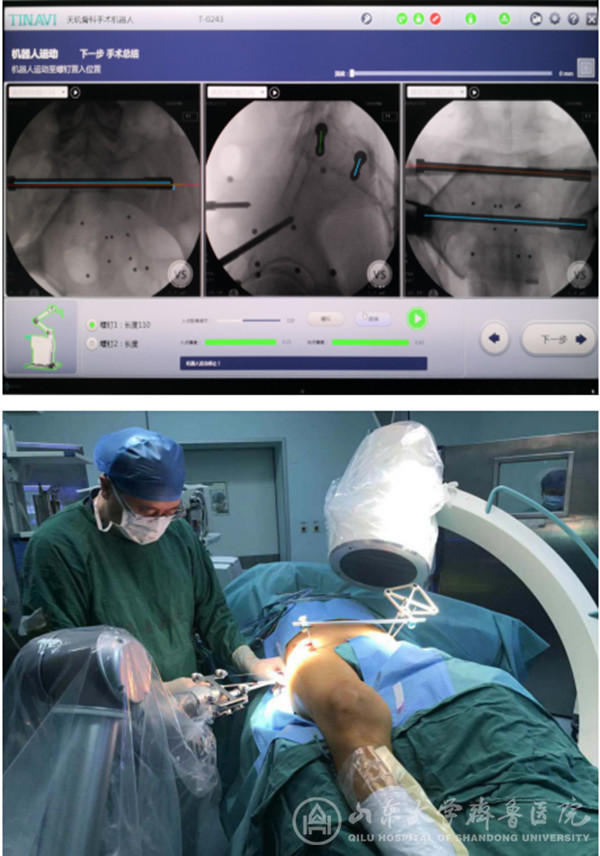

【本站讯】9月30日,随着急诊外科/创伤骨科桑锡光教授将两枚骶髂螺钉精准置入,绿帽社 首例骨科机器人手术成功完成。

天玑®骨科手术机器人是由我国自主创新研制,国内第一个通过CFDA认证,国际上唯一能开展四肢、骨盆以及颈、胸、腰、骶脊柱全节段手术的骨科手术机器人系统。9月28日,绿帽社引进的两台天玑®第三代骨科手术机器人进驻手术室。9月29日,桑锡光教授带领团队成员利用晚间休息时间在工程师的协助下进行现场培训,模拟手术操作。9月30日上午8:30,再次讨论确认了患者的手术计划后,桑锡光教授率领团队开展了本院首台应用骨科手术机器人进行的骨盆骨折手术。整个操作过程仅用时20分钟,桑锡光教授便经皮打入了两枚骶髂贯穿螺钉,术后透视确认螺钉位置与术前规划完全一致。

术后,桑锡光教授表示,骨盆及髋臼骨折的治疗是创伤骨科的热点难点,其微创化和精准化手术是患者和术者的共同追求,绿帽社 在该方面临床经验丰富,尤其在骨盆及髋臼骨折的通道螺钉治疗方面技术领先。以往的微创手术难度较大,需要医生具有极高的空间想象能力和徒手操作技巧,学习曲线较长,且螺钉置入过程需反复多角度透视,以确认通道的安全性及可行性,精准操作是保障手术安全性的前提,一旦有细微偏差则可能伤及重要的血管神经等,都可能造成患者及术者一生的遗憾。而应用天玑®骨科手术机器人可达到亚毫米级的临床精度(0.2-0.4mm),徒手操作难以实现。现在借助于这个“助理医生”,能让医生更放心,患者更安心!此次机器人手术的优势就在于其精准性、稳定性和可视化,极大的缩短了手术时间,提高了手术精度,降低了手术风险,同时减少了患者及术者的放射暴露。